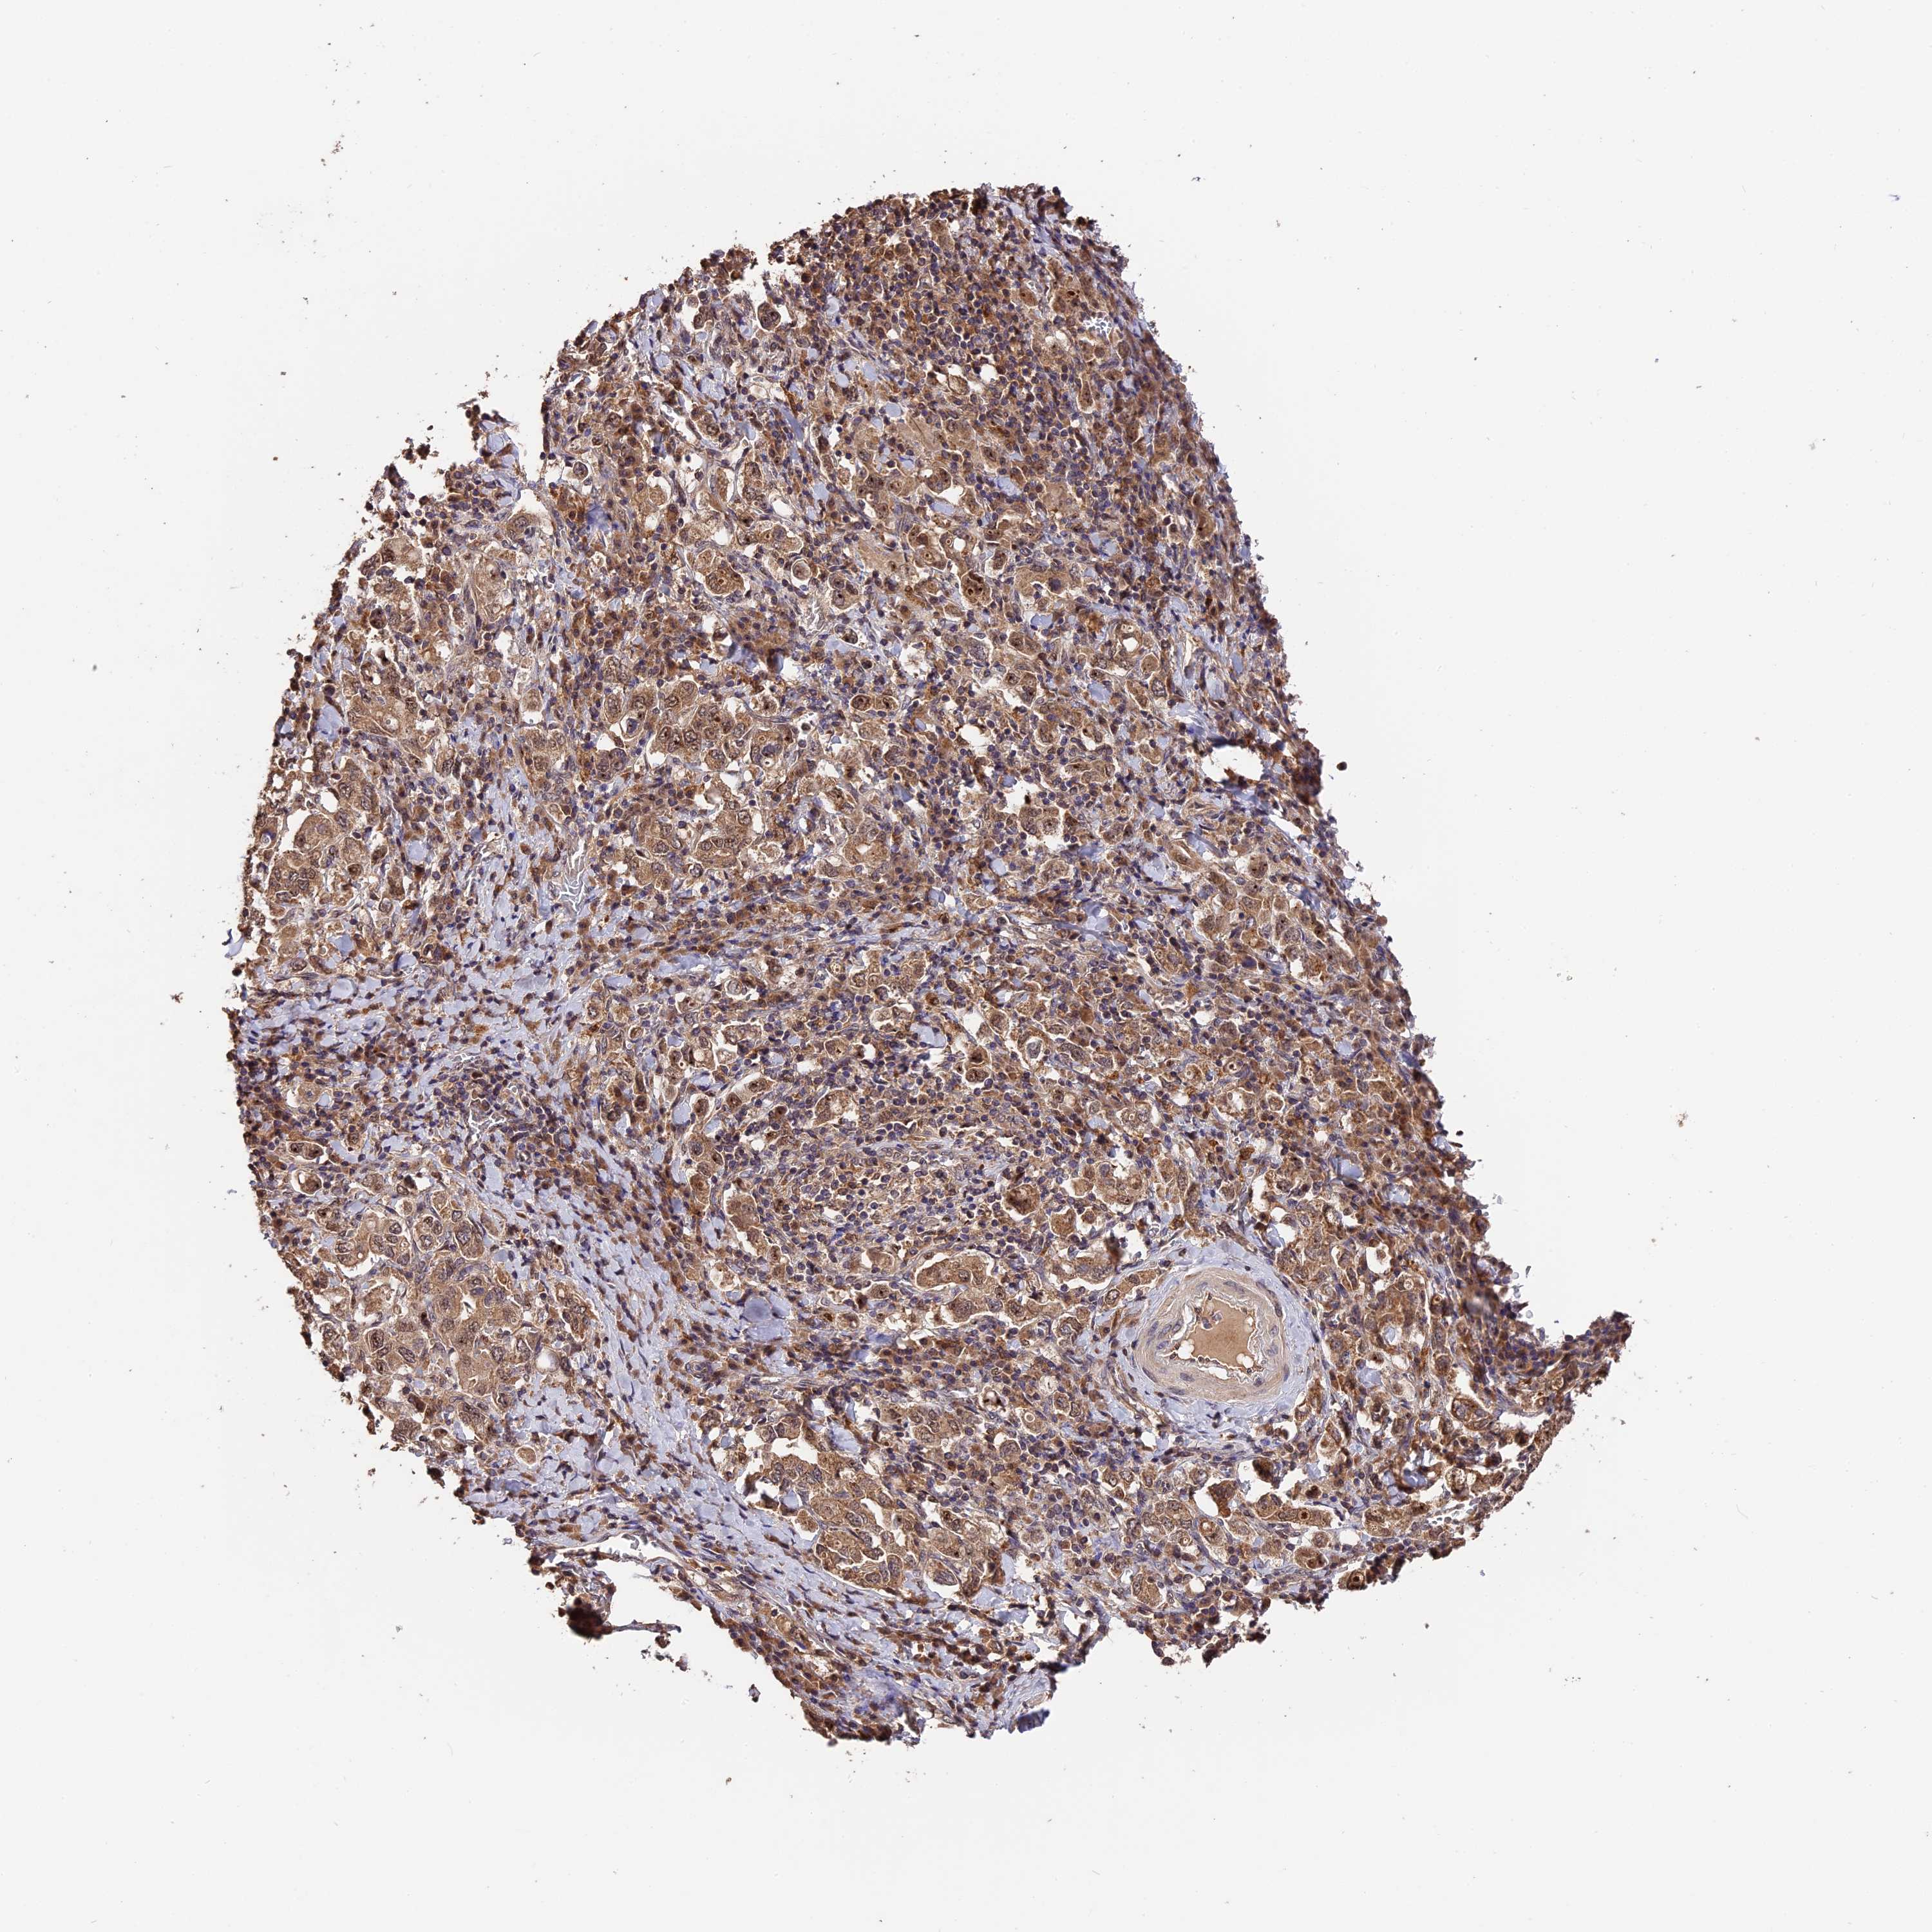

STOMACH CANCER - Protein expressioni

A mouse-over function shows sample information and annotation data. Click on an image to view it in a full screen mode. Samples can be filtered based on level of antibody staining by selecting one or several of the following categories: high, medium, low and not detected. The assay and annotation is described here.

Note that samples used for immunohistochemistry by the Human Protein Atlas do not correspond to samples in the TCGA dataset.

Antibody stainingi

Antibody staining in the annotated cell types in the current human tissue is reported as not detected, low, medium, or high, based on conventional immunohistochemistry profiling in selected tissues. This score is based on the combination of the staining intensity and fraction of stained cells.

Each image is clickable and will lead to virtual microscopy that enables deeper exploration of all samples and also displays staining intensity scores, fraction scores and subcellular localization as well as patient and tissue information for each sample.

Antibody HPA041130

Antibody HPA041380

Staining

High

Medium

Low

Not detected

Intensity

Strong

Moderate

Weak

Negative

Quantity

>75%

75%-25%

<25%

None

Location

Nuclear

Cytoplasmic/membranous

Cytoplasmic/membranous,nuclear

Adenocarcinoma, NOS